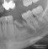

1. Chirurgie orala

Aditie osoasa – pregatirea sitului impla ..